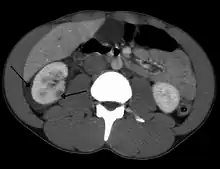

| Abdominal trauma resulting in a right kidney contusion (open arrow) and blood surrounding the kidney (closed arrow) as seen on CT | |

Kidneys

The kidneys may also be injured; they are somewhat but not completely protected by the ribs.[6] Kidney lacerations and contusions may also occur.[13] Kidney injury, a common finding in children with blunt abdominal trauma, may be associated with bloody urine.[13] Kidney lacerations may be associated with urinoma or leakage of urine into the abdomen.[4] A shattered kidney is one with multiple lacerations and an associated fragmentation of the kidney tissue.[4]